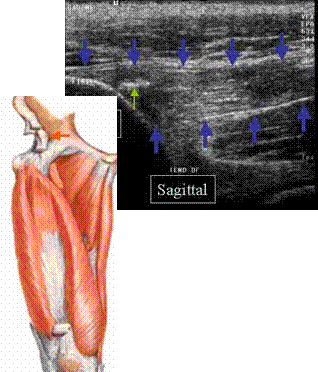

TENDINOPATIE

CALCIFIANTA

A TENDONULUI DIRECT AL MUSCHIULUI DREPT FEMURAL

Insertia tendonului direct al m. drept femural

pe spina Iliaca

antero inferioara →

Tendonul este ingrosat, hipoecogen →

cu mici calcificari →